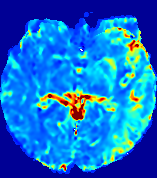

Slice #1Slice #2Slice #3Slice #4Slice #5Slice #6Dgtsuperscript𝐷gtD^{\text{gt}}Refer to captionRefer to captionRefer to captionRefer to captionRefer to captionRefer to caption(a)Refer to captionRefer to captionRefer to captionRefer to captionRefer to captionRefer to caption(b)Refer to captionRefer to captionRefer to captionRefer to captionRefer to captionRefer to caption(c)Refer to captionRefer to captionRefer to captionRefer to captionRefer to captionRefer to caption(d)Refer to captionRefer to captionRefer to captionRefer to captionRefer to captionRefer to caption(e)Refer to captionRefer to captionRefer to captionRefer to captionRefer to captionRefer to caption(f)Refer to captionRefer to captionRefer to captionRefer to captionRefer to captionRefer to captionRefer to caption000.060.060.060.120.120.120.180.180.180.240.240.240.300.300.30(mm2/s)𝑚superscript𝑚2𝑠(mm^{2}/s)

Figure 13: PIANO effectiveness and robustness testing: diffusion imaging via diffusion. Top row shows Dgtsuperscript𝐷gtD^{\text{gt}} used for simulating the ground truth pure diffusion. (a)-(f) refer to the results for D𝐷D estimated from the ground truth pure diffusion image time-series where Rician noise at levels 0%, 2%, 4%, 6%, 8%, 10% was added respectively.

Note this is likely not a spatially representative ground-truth for perfusion imaging, as it measures different effects from diffusion imaging. However, we still use it as a quasi-realistic pattern of diffusivity in the brain. We also added 2%, 4%, 6%, 8%, 10% levels of Rician noise to obtain simulations of ‘Diffusion Imaging’. The estimated Destsuperscript𝐷estD^{\text{est}} given concentrations of all noise levels for one patient are shown in Fig. 13, PIANO estimation results for all patients are summarized in Fig. 11 (b). Again, PIANO demonstrates its capability to recover the underlying diffusion field. In Fig. 13, when the noise level is increasing, some noisy patterns indeed appear in the associated Destsuperscript𝐷estD^{\text{est}}. Note that the ground truth diffusivity applied in this simulation experiment is about ten times larger than the diffusivity estimated in reality (Fig. 3, Fig. 4).